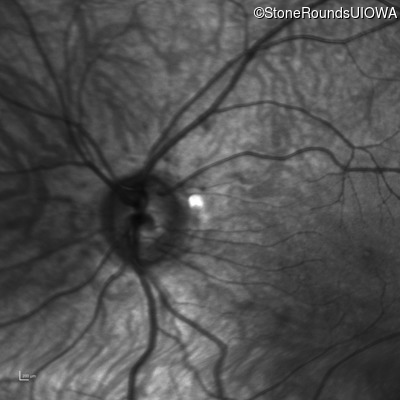

Infrared Fundus Photograph - Right - 10/160 sc

Exemplar

Infrared Fundus Photograph - Left - 10/200 sc